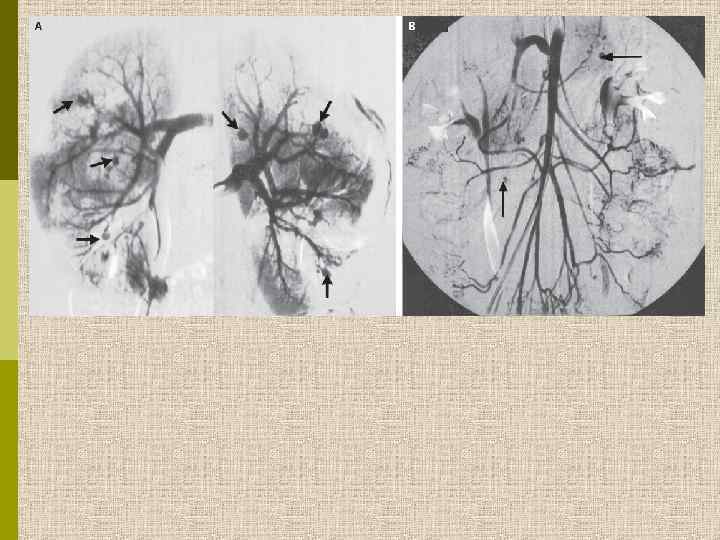

Артериограмма почки при узелковом полиартериите. Микроаневризмы мелких артерий, окклюзия больших артерий. Rose BD, 1987

Почечные аневризмы при узелковом полиартериите, ассоциированном с гепатитом В Chauveau D. , Christophe J-L. N Engl J Med 1995; 332: 1070

Malaise, anorexia, progressive limb paresis and multiple defects in the kidneys W. Smit, J. Reekers, M. J. Schultz January 2005, vol. 63, no. 1, 32 Academic Medical Centre, Amsterdam, the Netherlands